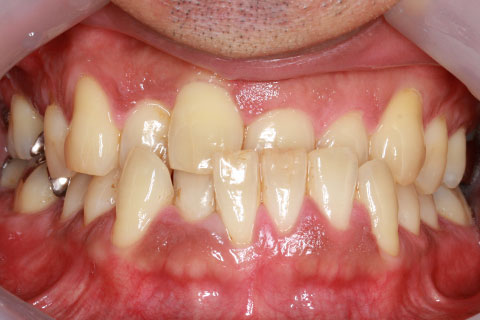

ハーフリンガル矯正3:上の歯のみ舌側矯正で治療(矯正期間24ヶ月)

治療前

治療中(開始直後)

治療中(開始半年後)

治療後

- 年齢・性別

- 25歳女性

- 治療期間

- 2年0ヶ月

- 抜歯

- 上下4番抜歯

- 治療費

- 110万円

- 治療内容

- 施術の副作用(リスク)

- 表側矯正と比較して、力学的な操作性が複雑なため、ボーイングエフェクトを起こしやすい。